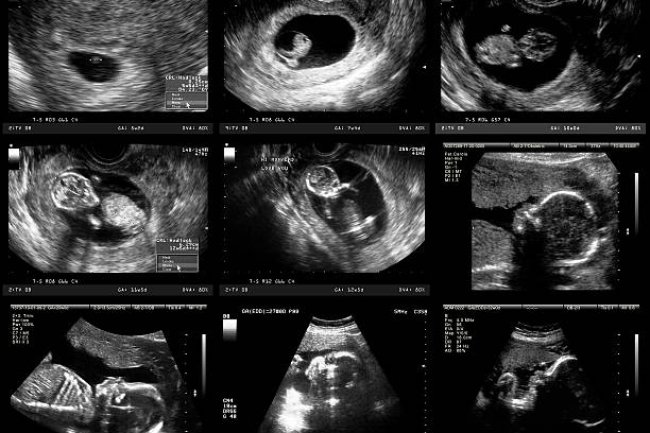

Pregnancy week by way of week

The opportunity of an X-ray all through being pregnant causing harm to your unborn baby may be very small. Generally, the blessings...